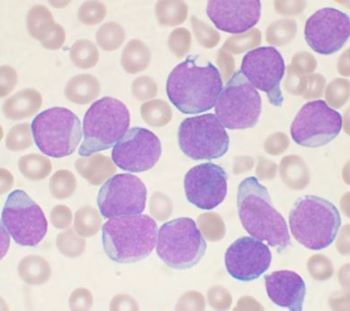

A 52-year-old man with HIV presents with weight loss and supraclavicular mass. Biopsy shows large, atypical cells with the following phenotype: CD45+, CD20-, PAX5 weak, CD3-, CD15-, CD138-, EBER-ISH+. H&E and stains for CD30 and CD79a are shown.

This is a case of EBV-positive diffuse large B-cell lymphoma associated with immune deficiency with an unusual phenotype. B-cell markers are downregulated with negative CD20 and weak expression of PAX5 and CD79a. The unusual phenotype combined with CD30 positivity raises the possibility of Classic Hodgkin lymphoma (CHL). However, the neoplastic cells are positive for CD45 and negative for CD15, making CHL unlikely. Plasmablastic lymphoma was excluded by CD138 negativity.